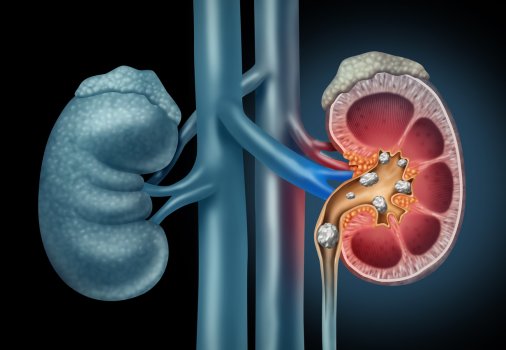

Οι καρδιαγγειακές παθήσεις συνδέονται με υψηλότερο κίνδυνο ανάπτυξης νεφρικής ανεπάρκειας.Τα ευρήματα, υπογραμμίζουν τη σημασία της προστασίας της νεφρικής υγείας των ατόμων που έχουν διαγνωστεί με καρδιαγγειακές παθήσεις.

Κατά τη διάρκεια μιας μέσης παρακολούθησης 17,5 ετών, 2.598 ασθενείς νοσηλεύθηκαν με καρδιαγγειακή νόσο -1.269 με καρδιακή ανεπάρκεια, 1.337 με κολπική μαρμαρυγή, 696 με στεφανιαία νόσο και 559 με εγκεφαλικό επεισόδιο. Επίσης 210 ασθενείς εμφάνισαν νεφρική ανεπάρκεια.

Η εκδήλωση καρδιαγγειακής νόσου σχετίστηκε με υψηλότερο κίνδυνο νεφρικής ανεπάρκειας -ο υψηλότερος κίνδυνος προήλθε από την καρδιακή ανεπάρκεια. Οι συμμετέχοντες που νοσηλεύονταν με καρδιακή ανεπάρκεια είχαν 11,4 φορές μεγαλύτερο κίνδυνο εμφάνισης νεφρικής ανεπάρκειας σε σχέση με τα υγιή άτομα.

Τα άτομα με ιστορικό καρδιαγγειακής νόσου θα πρέπει να αναγνωρίζονται ως πληθυσμός υψηλού κινδύνου για νεφρική ανεπάρκεια. Σε αυτό το πλαίσιο, οι γιατροί θα πρέπει να γνωρίζουν τις καρδιαγγειακές παθήσεις ως σημαντική κατάσταση κινδύνου και έτσι να ελαχιστοποιούν τις τοξικές για τους νεφρούς θεραπείες σε τέτοια άτομα, ανέφερε ο Ishigami. “Επιπλέον, τα ευρήματά μας μπορεί να έχουν επιπτώσεις στην παρακολούθηση της λειτουργίας των νεφρών, παρόλο που οι τρέχουσες κατευθυντήριες γραμμές για τις καρδιαγγειακές παθήσεις δεν ορίζουν απαραιτήτως τη συχνότητα εκτίμησης της νεφρικής λειτουργίας μετά από την εμφάνιση καρδιαγγειακής νόσου”.